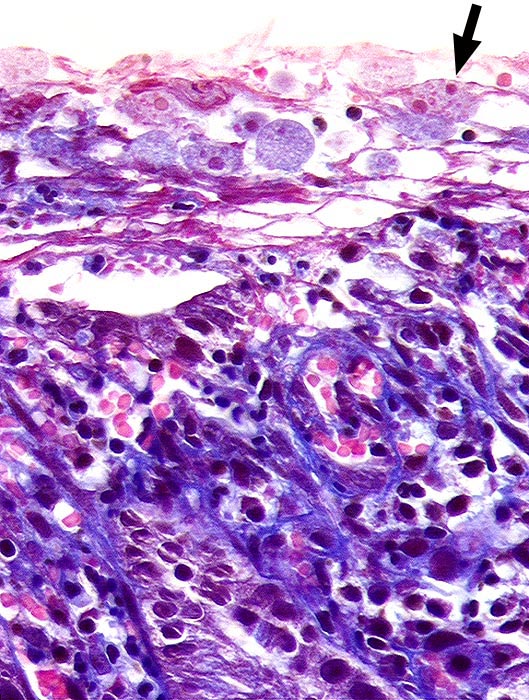

Amöbenkolitis

Entzündung infektiös

Kolon

Pathologischer Befund